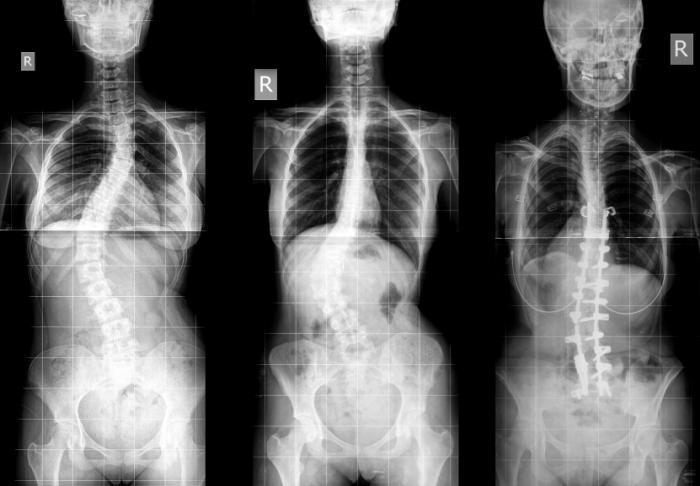

Chụp X-quang

Vị trí chụp từ phía trước ở tư thế đứng để đo sự thẳng hàng, độ cong và sự cân đối của các phân đoạn cột sống, xương chậu và hông.

Cong-veo-cot-song Vẹo cột sống nhìn qua phim chụp X-quang